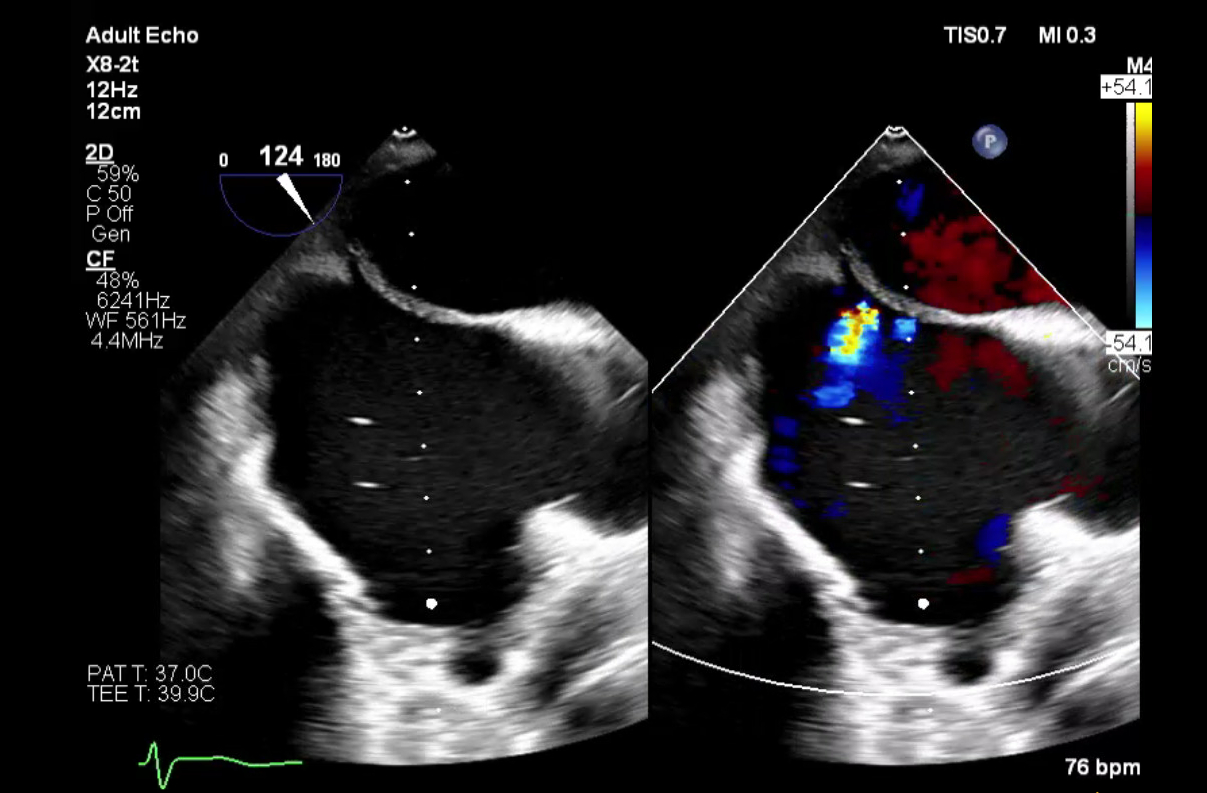

Abstract Body (Do not enter title and authors here): Case Description: A 54-year-old male with ESRD on hemodialysis, tricuspid valve endocarditis status post bioprosthetic valve replacement, and atrial fibrillation status post catheter ablation one month prior, underwent elective Watchman device implantation. Following successful device placement, the patient continued to require ventilator support. Intra-procedural TEE revealed a known iatrogenic atrial septal defect (iASD) from prior ablation with a moderate right-to-left shunt and a peak gradient of 16 mmHg. The bioprosthetic tricuspid valve demonstrated severe stenosis. Additional findings included moderate-to-severe tricuspid regurgitation, a severely dilated right atrium, and preserved left ventricular ejection fraction. The patient remained ventilator-dependent and developed septic shock within 24 hours secondary to pneumonia. Despite dialysis and antibiotic therapy, hypoxia persisted. The right-to-left shunt across the iASD, driven by elevated right atrial pressure from severe tricuspid stenosis, was identified as a major contributor. On hospital day 9, the patient underwent transcatheter tricuspid valve replacement. Following the procedure, he improved rapidly, was extubated within 48 hours, and was discharged four days later, off supplemental oxygen and ambulating with support. At 45-day follow-up, he remained asymptomatic. TEE showed a well-functioning tricuspid prosthesis, moderately dilated right atrium, and two small ASDs with predominantly left-to-right flow.